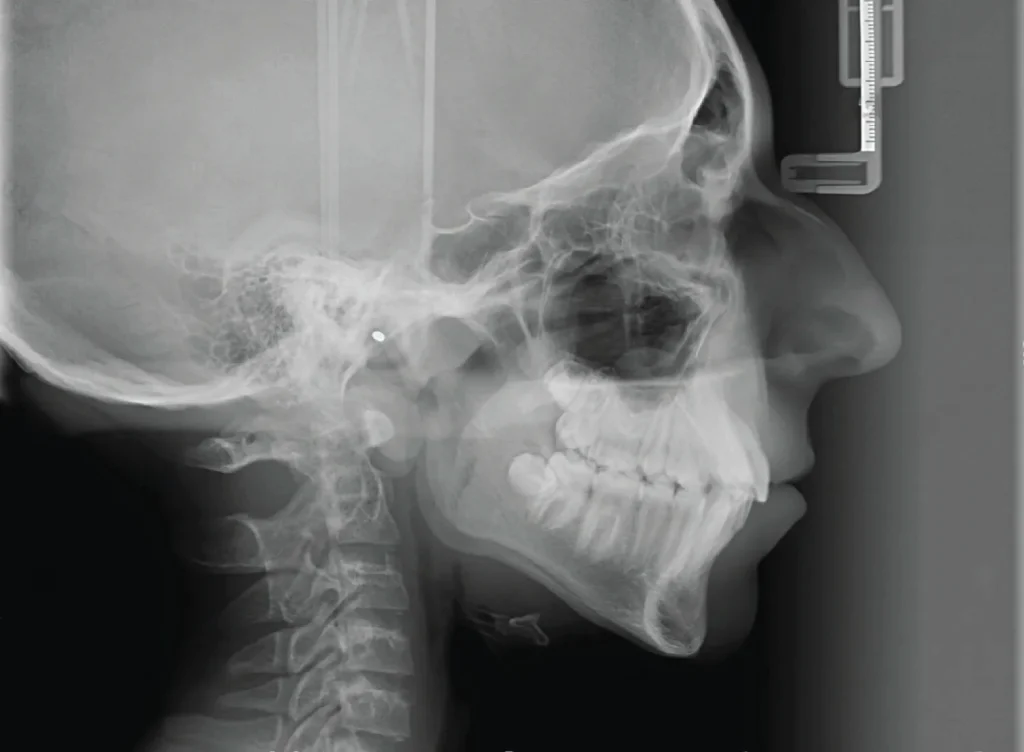

Cephalometric xray

Think of it as a special camera that captures a detailed image of the side of your face. Unlike traditional X-rays, this doesn’t involve any uncomfortable films in your mouth, making it perfect for patients with sensitive gag reflexes.

Cephalometric X-rays are typically taken using a panoramic X-ray machine equipped with a special cephalometric film holder. You’ll stand comfortably within the machine while a technician positions your head for optimal imaging. The machine arm then moves swiftly to capture a clear picture of your facial profile. These images can be magnified for exceptional clarity, ensuring no detail goes unnoticed.

• Unveiling a Range of Oral Concerns: Cephalometric X-rays are highly versatile, helping identify various dental issues like malocclusions (bad bites), jawbone fractures, cavities, and more. It also allows dentists to assess your cheekbones and jaws, along with measuring key bony structures for treatment planning.